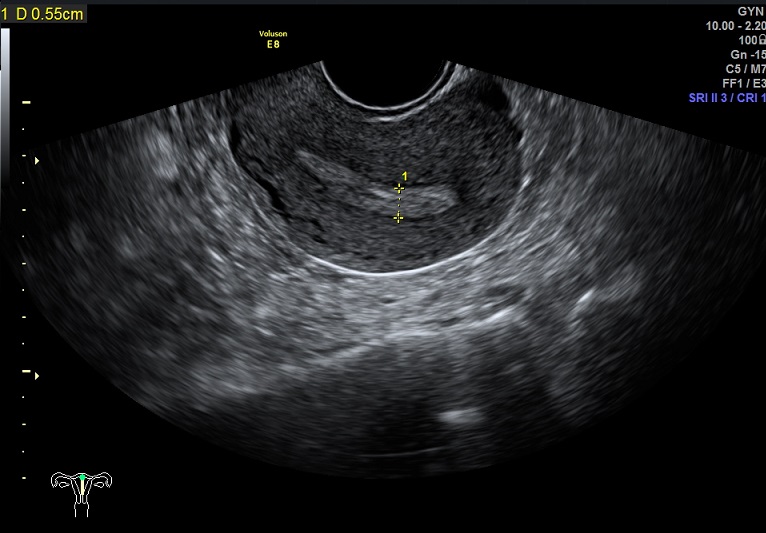

女性,28岁,继发性不孕2年。

2015-1-28 月经第24天检查

内膜厚0.6cm

内膜血流:1级